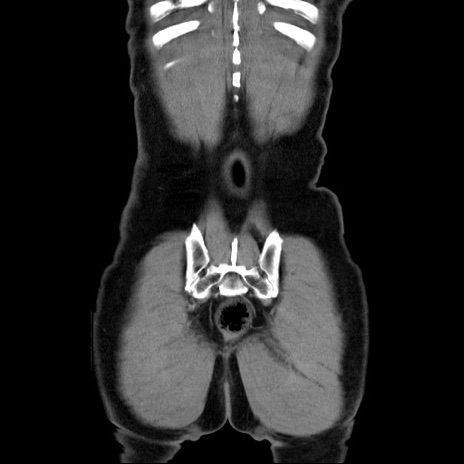

横断像

【症例】60歳代 男性

【主訴】右鼠径部膨隆

【現病歴】1年程前より右鼠径部膨隆あり。自己にて還納可能だったため放置していた。3時間前より右鼠径部の脱出を認め、還納困難となり受診。

【既往歴】高血圧

【身体所見】右鼠径部に小児頭大の膨隆あり。弾性硬であり、用手還納は困難。左鼠径部にも膨隆を認める。脱出はなし。